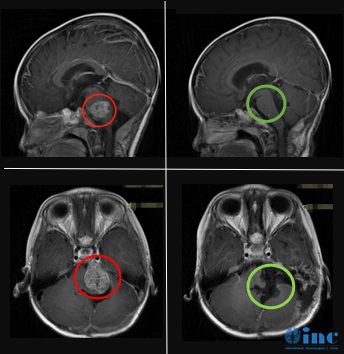

巴教授术前术后片子对比:肿瘤全切(红色术前,绿色术后)